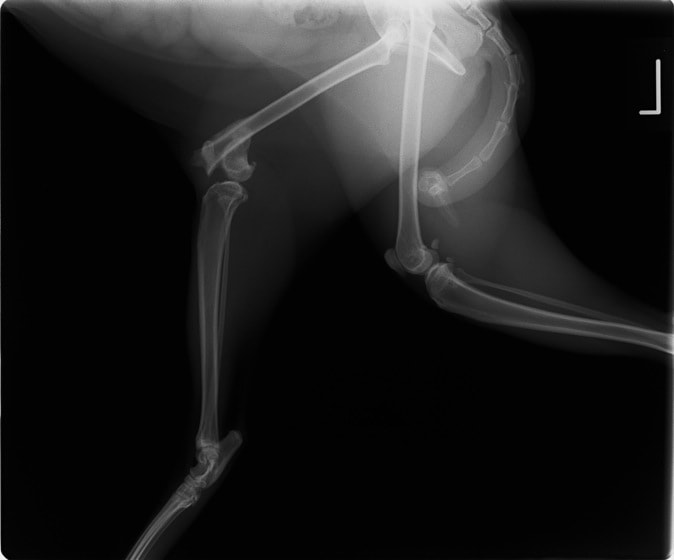

症例3:キルシュナーワイヤーのピンニングによる整復

ペルシャ猫 11ヶ月齢 雄

他院にて左大腿骨遠位の成長板骨折(salter-harrisⅠ型)が認められており、治療相談を目的として来院。当院にて、キルシュナーワイヤーを用いたピンニングにより骨折部位の整復を行いました。術後の経過は良好で、現在も経過観察中です。

術前レントゲン

術後レントゲン

機器

Arthrex社のターゲティングデバイスを用いてピンニングの位置を調整することで、確実な固定を行っています。当院ではこの手術器具以外にも、人の手術にも使用される様々な器具を導入し、手術精度を高め、また医療メーカーと新しい器具の開発、試作にも取り組んでおります。